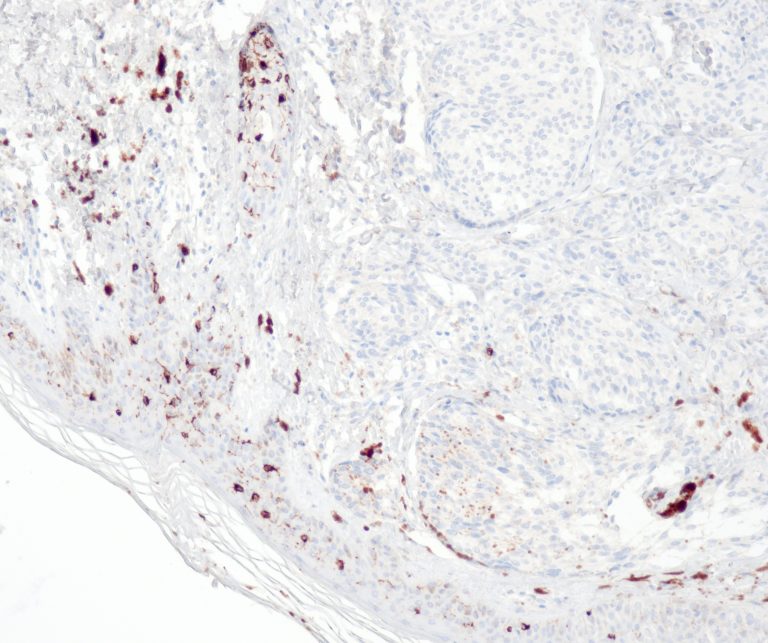

Vascular Pathology

Gastrointestinal (GI) Pathology

General Marker

Breast Pathology

Endocrine Pathology

Gynecological Pathology

Neuropathology

Infection Markers

Lung Pathology

Urinary Tract Pathology

Transplantation Pathology

Soft Tissue Pathology

Hematopathology